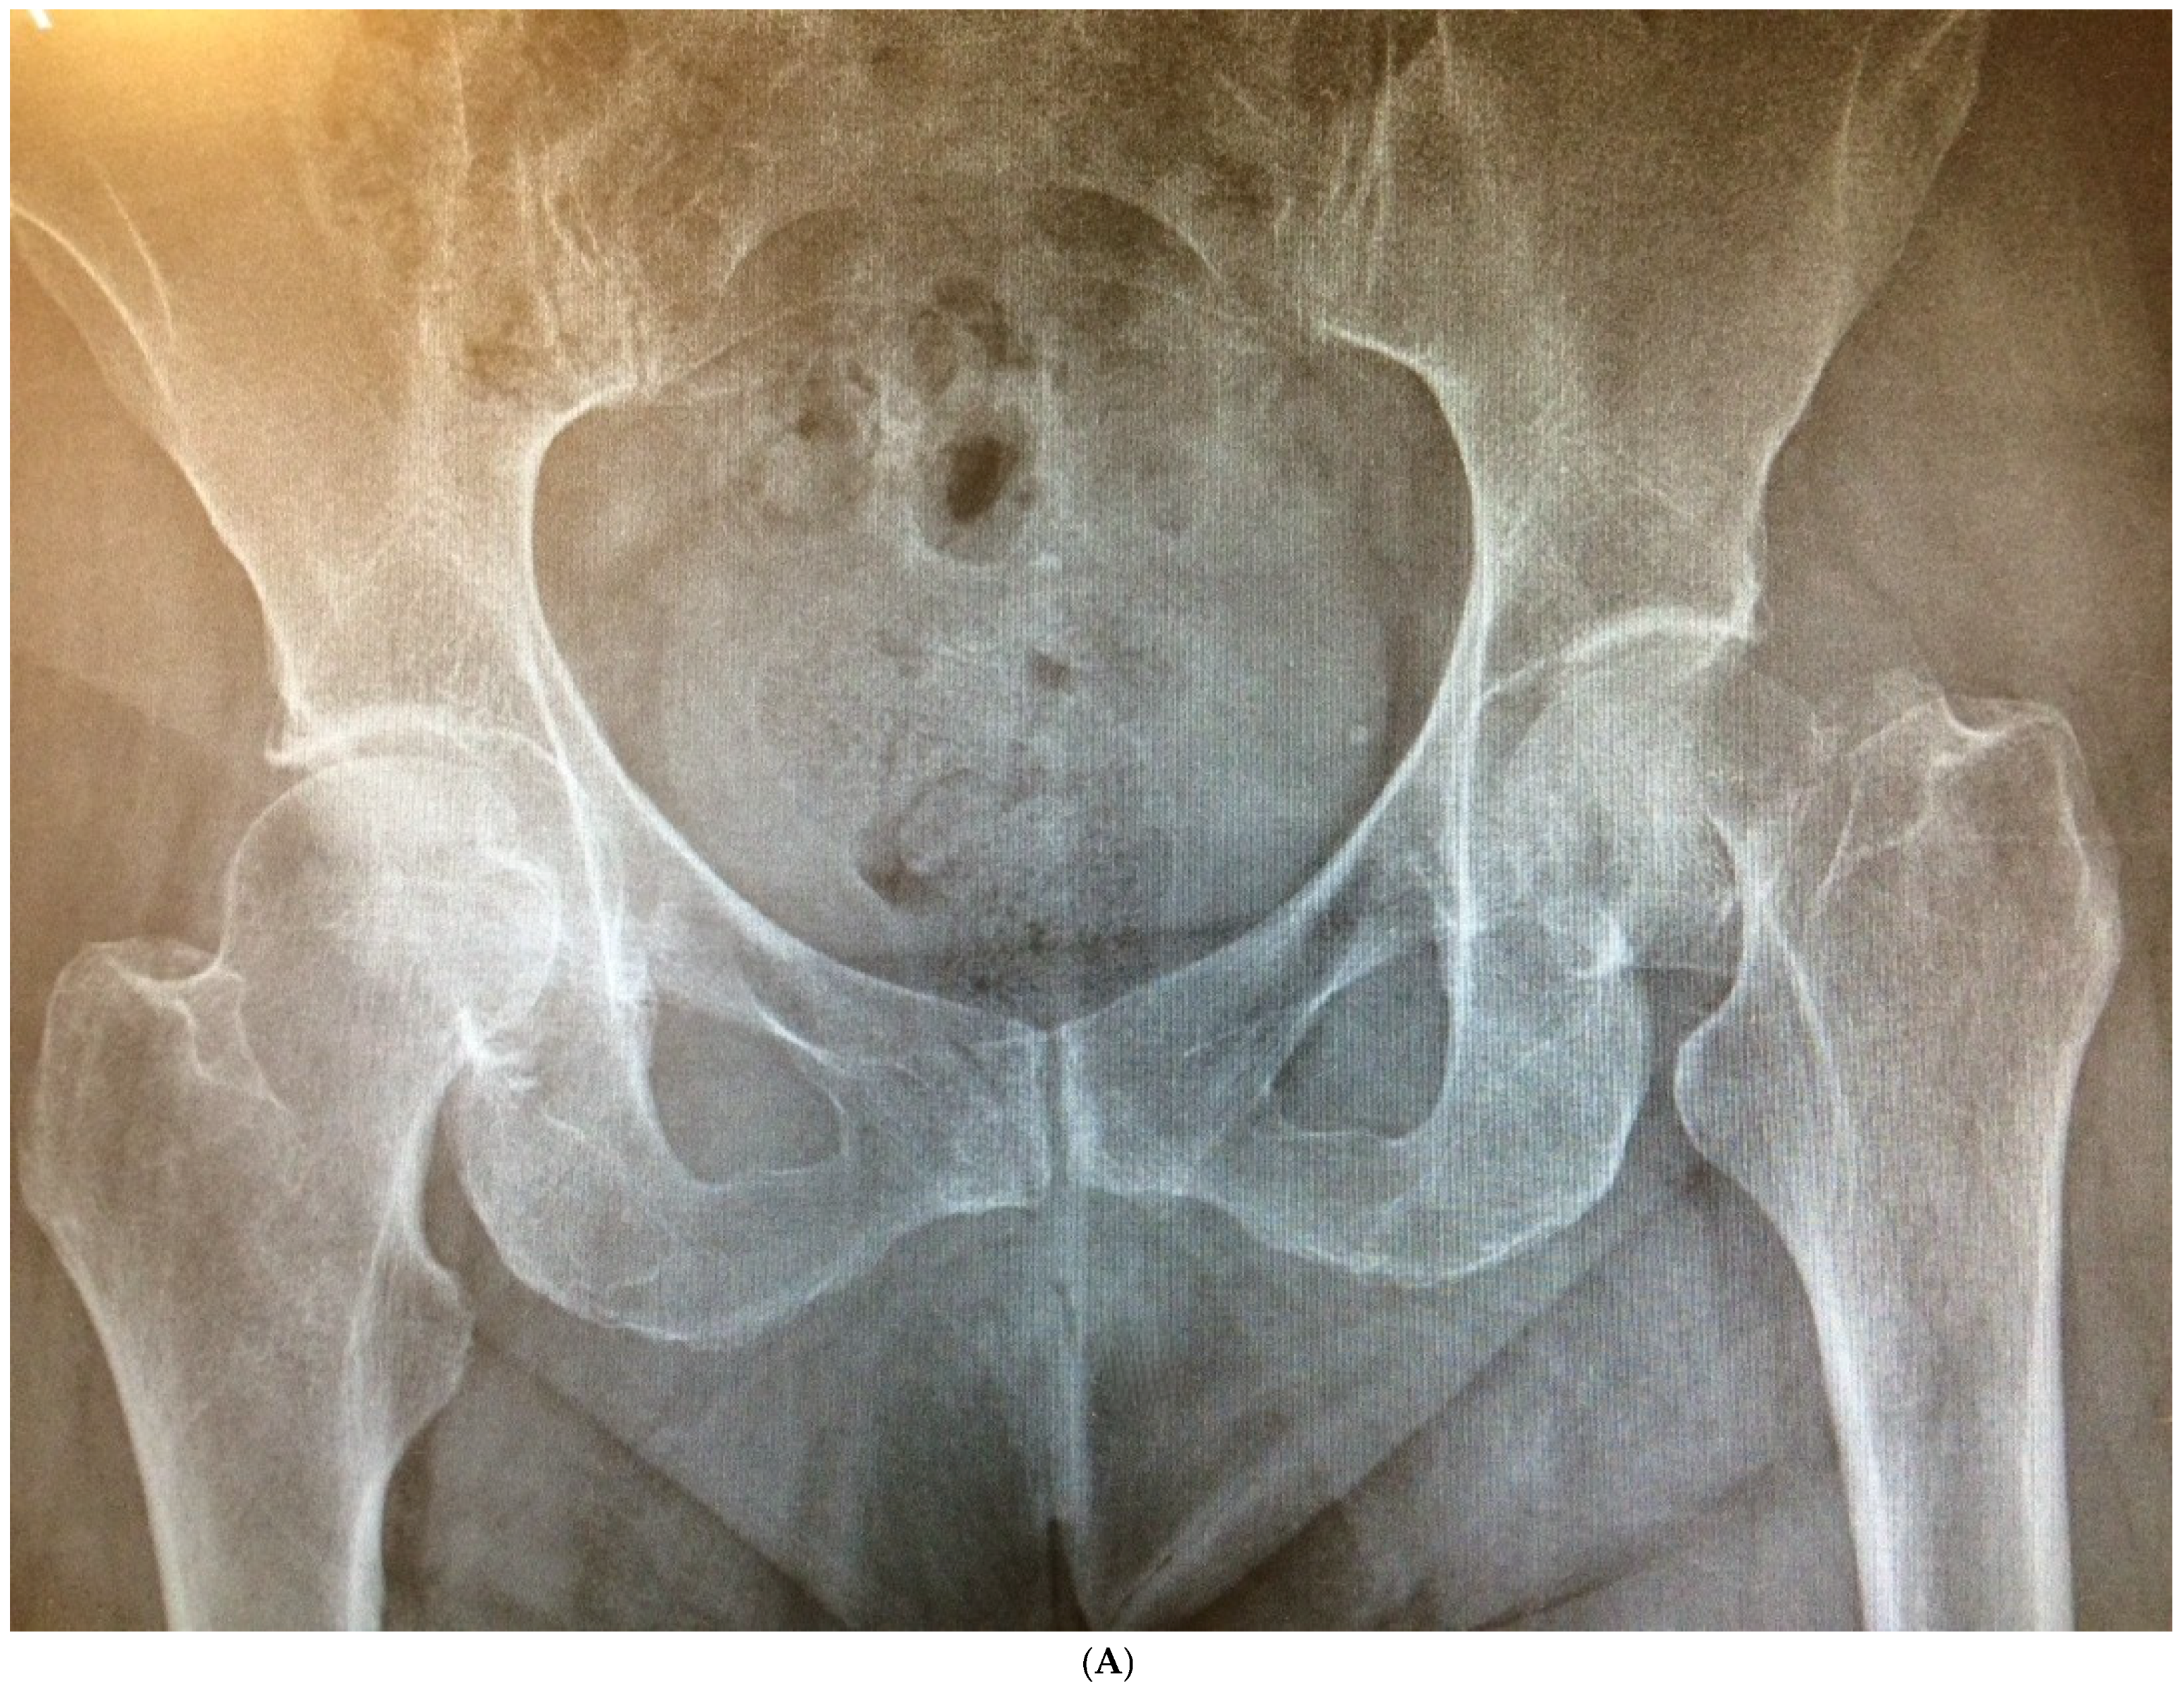

Figure 4.

(A) Preoperative anteroposterior X-ray. Left hip sustained a displaced femoral neck fracture. (B) Postoperative anteroposterior X-ray (CSS group). Femoral stem shows osseointegration and good proximal loading, with no bone resorption at final follow-up. (C) Postoperative lateral X-ray (CSS group). At final follow-up, the stem shows no subsidence and good fixation.